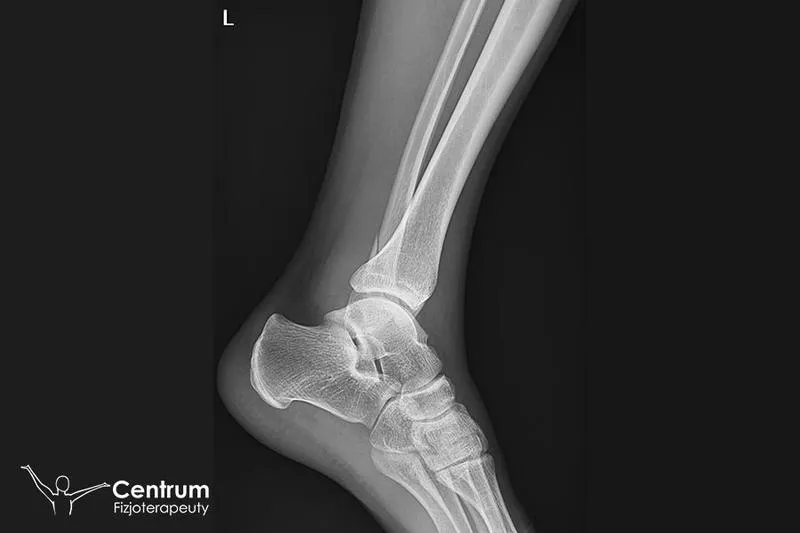

Złamanie kostki to uraz, który skutecznie wyłącza nas z codziennych działań. Aby powrócić do pełnej sprawności, konieczne staje się zaangażowanie w rehabilitację. Proces rehabilitacji dzieli się na kilka właściwych etapów, które zazwyczaj rozpoczynamy po zdjęciu gipsu lub ortezy. To właśnie rehabilitacja odgrywa kluczową rolę w odzyskiwaniu pełnej funkcji stawu. W większości przypadków rehabilitacja trwa od trzech do sześciu miesięcy, ale warto pamiętać, że indywidualne predyspozycje pacjenta oraz charakter złamania znacząco wpływają na tempo tego procesu.

Rehabilitacja po złamaniu kostki pełni kluczową rolę w przywracaniu pełnej sprawności. Ten powszechny uraz potrafi na dłuższy czas wyłączyć nas z codziennych aktywności, dlatego ważne jest, aby podejść do rehabilitacji z odpowiednią starannością. Właściwe działania rehabilitacyjne nie tylko pozwalają na szybkie odzyskanie mobilności, ale również minimalizują ryzyko powikłań, które mogą negatywnie wpływać na życie przez wiele lat. Warto zrozumieć, że rehabilitacja stanowi całościowy proces regeneracyjny, a nie tylko zbiór ćwiczeń.